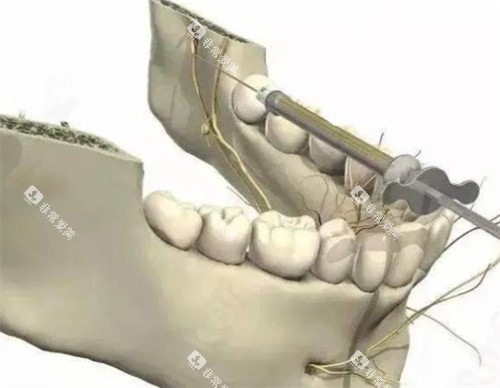

口腔颌面外科的医生们具备丰富的手术经验,能够开展各类口腔颌面外科手术,如拔牙、口腔瘤子切除、颌骨骨折修复等。

在手术过程中,他们看重手术技巧和患者的术后修复,尽可能减少手术创伤,提高患者的生活质量。